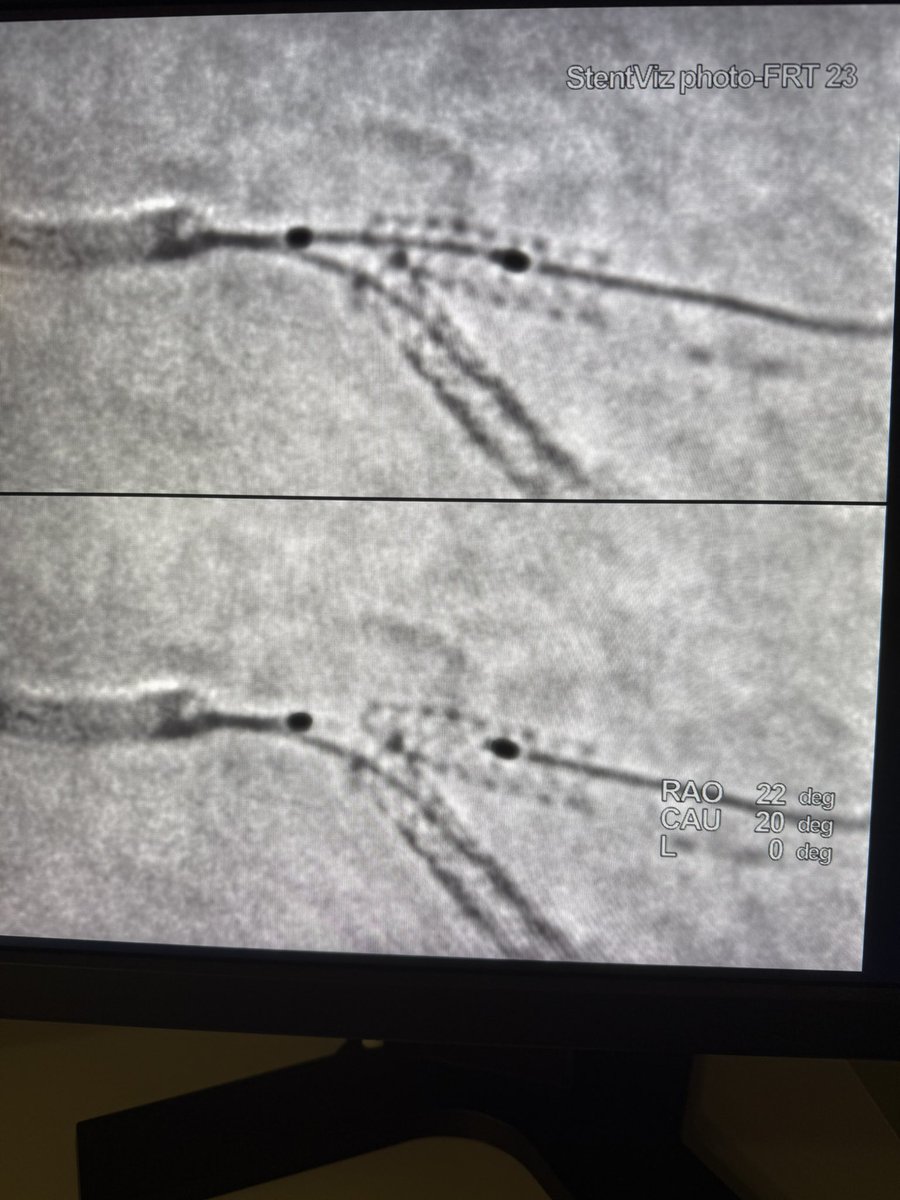

F/u to previous post. Stent boost is terrific! Clearly defined the problem. Prep a cutter and high psi NCs. 3.0 agent and a KBI to finish.

2

0

9